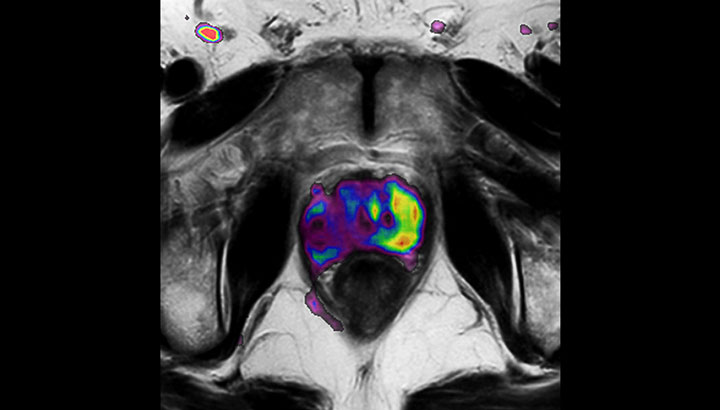

La possibilité de régler les contrastes peut fournir des informations encore plus précieuses sur les caractéristiques et l’étendue de la tumeur afin d’en faciliter la délimitation et offrir également des possibilités de stratégies d’augmentation de dose.

En plus de l’imagerie anatomique, l’IRM permet d’obtenir des informations fonctionnelles utiles pour la détection et la délimitation des tumeurs, ainsi que pour le suivi de la réponse au traitement.

Les images pondérées en diffusion (DWI), par exemple, permettent de distinguer des zones d’intensité de signal élevée dans les tissus mous qui indiquent la mobilité réduite de l’eau (c-à-d. la diffusion) d’une tumeur et peuvent également être utilisées pour identifier des ganglions lymphatiques. Les modifications du coefficient de diffusion apparent (ADC) du tissu ou de la lésion peuvent fournir des informations permettant de prédire la réponse de la tumeur à la radiothérapie.